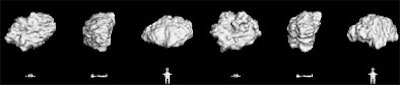

![]() |

| Volumetric analysis of nodule size shows a doubling rate of greater than 750 days. |